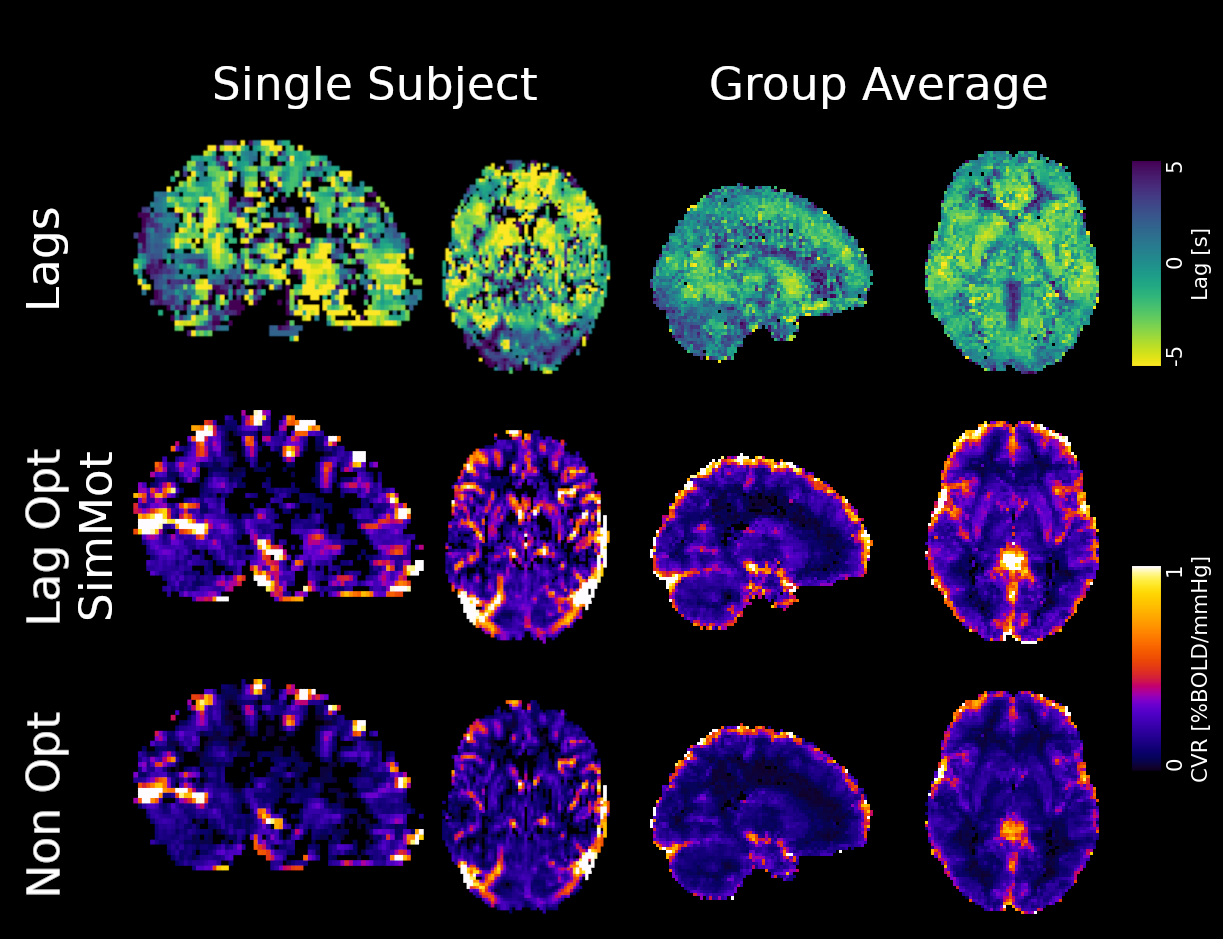

Methods: CVR and lag maps

CVR and lag maps: L-GLM with each lagged regressor and nuisance regressors (12 motion parameters and low frequency trends), voxelwise selection of the lagged model with highest explained variance (R²), normalisation to MNI152 template (2.5 mm isotropic)

We compared four pipelines:

- L-GLM with motion parameters (see above, SimMot): $$ Y = P_{ET}CO_2{hrf}_{vx} + Mot + Poly + n $$

- Non-optimised CVR map (measurement delay only, Non Opt): $$ Y = P_{ET}CO_2{hrf}_{bulk} +n $$

- L-GLM without motion parameters (NoMot): $$ Y = P_{ET}CO_2{hrf}_{vx} + n $$

- L-GLM without motion parameters, motion regressed out before (SeqMot): $$ [Y \perp (Mot,Poly)] = P_{ET}CO_2{hrf}_{vx} + n $$

Results: lag optimisation

Non optimising leads to underestimate the CVR, especially in subcortical areas.

Lag maps show anatomical consistency

Different lag responses, coherent with previous evidence (e.g. Putamen has earlier response than GM)

Area mostly affected by motion! →

Moia, Stickland, et al. 2020 (EMBC)